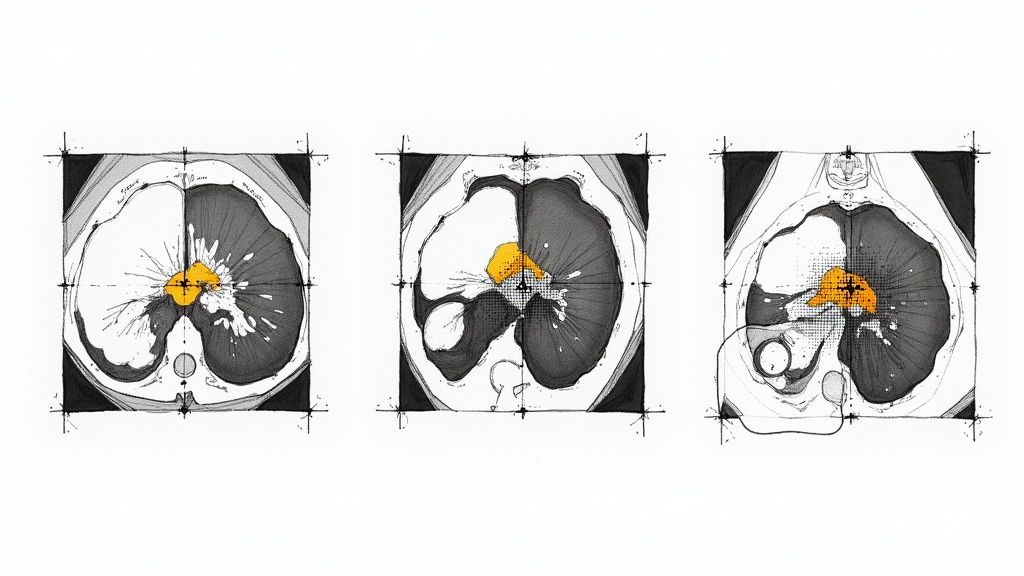

Nowhere is AI’s impact on diagnostics more obvious than in medical imaging. We’re seeing advanced computer vision models interpret incredibly complex scans—X-rays, CTs, MRIs—with a level of detail that often rivals, and sometimes surpasses, the human eye. This is a massive shift for fields like radiology, pathology, and dermatology.

The magic behind these systems is data. They are trained on enormous libraries of medical images, allowing them to learn the subtle visual cues of disease. Think of it as a radiologist who has studied millions of scans instead of thousands. This sheer volume of experience helps the AI spot tiny details, measure disease characteristics, and automatically map out anatomical structures. This, in turn, frees up clinicians to focus their expertise on the most challenging cases.

- Radiology: AI tools are busy flagging suspicious nodules in lung CT scans, identifying early signs of stroke in brain MRIs, and spotting hairline fractures in X-rays that might otherwise be missed during a hectic shift.

The performance of these AI systems isn't just on par with human experts; in many cases, it’s better. In cancer diagnostics, AI-powered tools have hit some incredible benchmarks, including a 93% match rate in detecting cancers from imaging analysis.

Consider a study from South Korea where an AI model achieved 90% sensitivity in diagnosing breast cancer from scans, a significant jump from the 78% managed by radiologists. That same model hit 91% accuracy in early detection, while human experts reached 74%. You can dig into the full research about these AI-powered diagnostic findings on scispot.com.